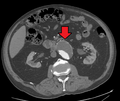

A ruptured AAA with an open arrow marking the aneurysm and the closed arrow marking the free blood in the abdomen

An axial contrast enhanced CT scan demonstrating an abdominal aortic aneurysm of 4.8 by 3.8 cm